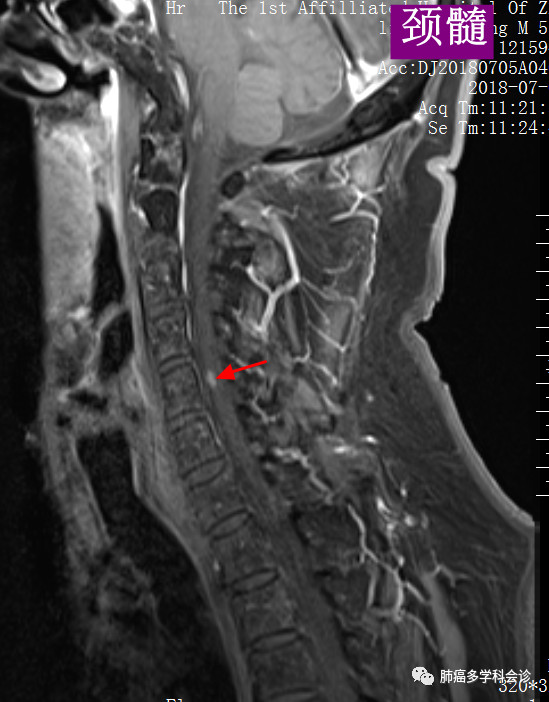

我们再把上图的局部进行放大,以更好显示转移灶:

颈部:3.jpg